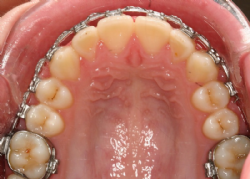

Die festsitzende Apparatur besteht normalerweise aus sogenannten Brackets, die auf die Zähne geklebt werden. Auf die Mahlzähne werden wegen der besseren Verankerungsmöglichkeit manchmal statt der Brackets ringförmige Bänder mit aufgeschweißten Röhrchen zementiert. In diese Bänder und Brackets werden hochelastische Drahtbögen eingesetzt, die die Zähne allmählich in die gewünschte Bogenform bewegen. Zusätzlich werden, je nach Erfordernis, Hilfsteile (elastische Ketten, Zug- und Druckfedern), verwendet. Daneben gibt es Sonderformen festsitzender Apparaturen, wie zum Beispiel festzementierte Platten für die Gaumennahterweiterung, Teilapparaturen auf wenigen Zähnen, und andere, die in ganz bestimmten Situationen Verwendung finden.